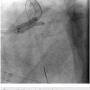

A 56-year-old man was on regular follow-up in our congestive heart failure (CHF) clinic for CHF with decreased ejection fraction. He gradually developed new Canadian Cardiovascular Society (CCS) III-IV anginal symptoms and had a cardiac catheterization revealing an angiographically significant, highly calcified proximal left anterior descending coronary artery (LAD) stenosis (90%) (Figure 1), intermediate left main (LM) disease (40-50%) (Figure 2), and complete occlusion of the distal right coronary artery (RCA) (Figure 3). Cardiac magnetic resonance imaging (MRI) revealed that the left ventricular apex and posterior walls might have limited viability.